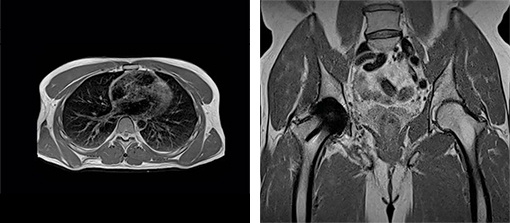

空気と組織の境界では,磁化率*2の大きな差により信号強度が著しく低下するため,高磁場MRIでは肺の検査が難しいのが現状。新しい磁場強度0.55テスラでは,磁化率アーチファクトが少ないため,肺のイメージングを改善し,新しい臨床応用を可能にする。

また,金属インプラントを挿入した被検者のMRI 検査も増加しているが,新しい磁場強度0.55テスラは金属アーチファクトの低減につながるため,インプラントイメージングにも有用である。

左:0.55テスラによる肺の検査画像 右:0.55テスラによるインプラントイメージング